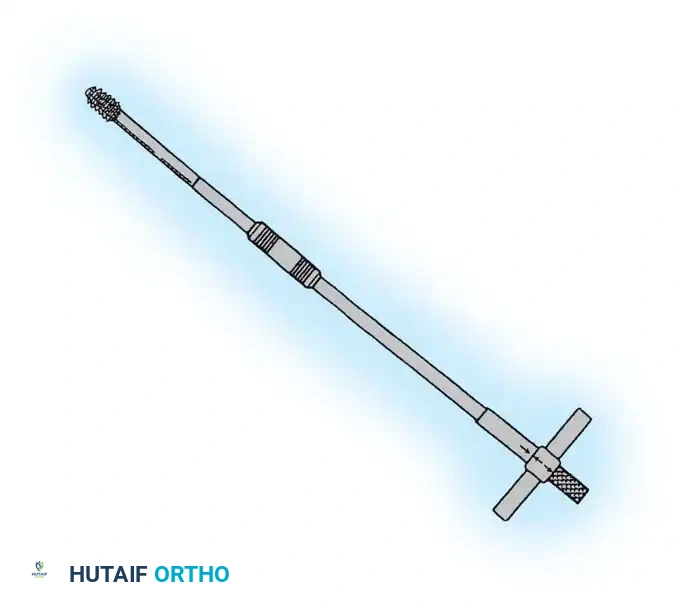

3. Guide Wire Placement

Whether using an SHS or a CMN, accurate placement of the guide wire into the femoral head is the most critical step of the operation.

Insertion of the guide wire. The wire must be positioned centrally in the femoral head on both AP and lateral views.

The Tip-Apex Distance (TAD):

Described by Baumgaertner, the TAD is the sum of the distance from the tip of the lag screw to the apex of the femoral head on both the AP and lateral radiographs. A TAD of less than 25 mm is strongly predictive of successful fixation; a TAD > 25 mm significantly increases the risk of screw cut-out.

4. Reaming and Lag Screw Insertion

Once the guide wire is perfectly positioned, the lateral cortex is opened, and the femoral neck is reamed over the wire.

Reaming of the femoral neck and head over the precisely placed guide wire, preparing the channel for the lag screw.

The lag screw is then inserted. It is crucial not to over-insert the screw, which can penetrate the articular cartilage, nor to under-insert it, which compromises fixation.